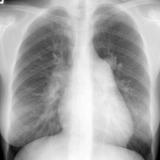

Pericardium

Album: Pericardium

Date: 03/17/2004

Size: 37 items

Views: 59849